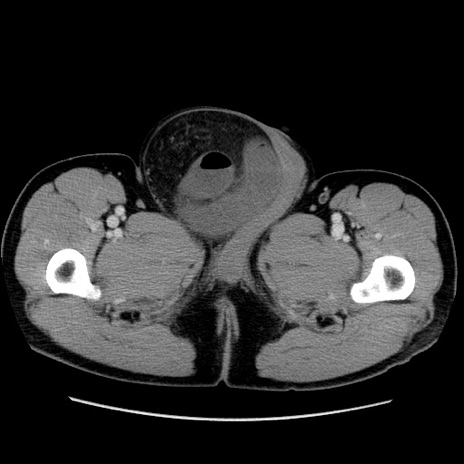

症例34(横断像)

【症例】60歳代 男性

【主訴】右鼠径部膨隆

【現病歴】1年程前より右鼠径部膨隆あり。自己にて還納可能だったため放置していた。3時間前より右鼠径部の脱出を認め、還納困難となり受診。

【既往歴】高血圧

【身体所見】右鼠径部に小児頭大の膨隆あり。弾性硬であり、用手還納は困難。左鼠径部にも膨隆を認める。脱出はなし。

【データ】WBC 15500、CRP 測定なし